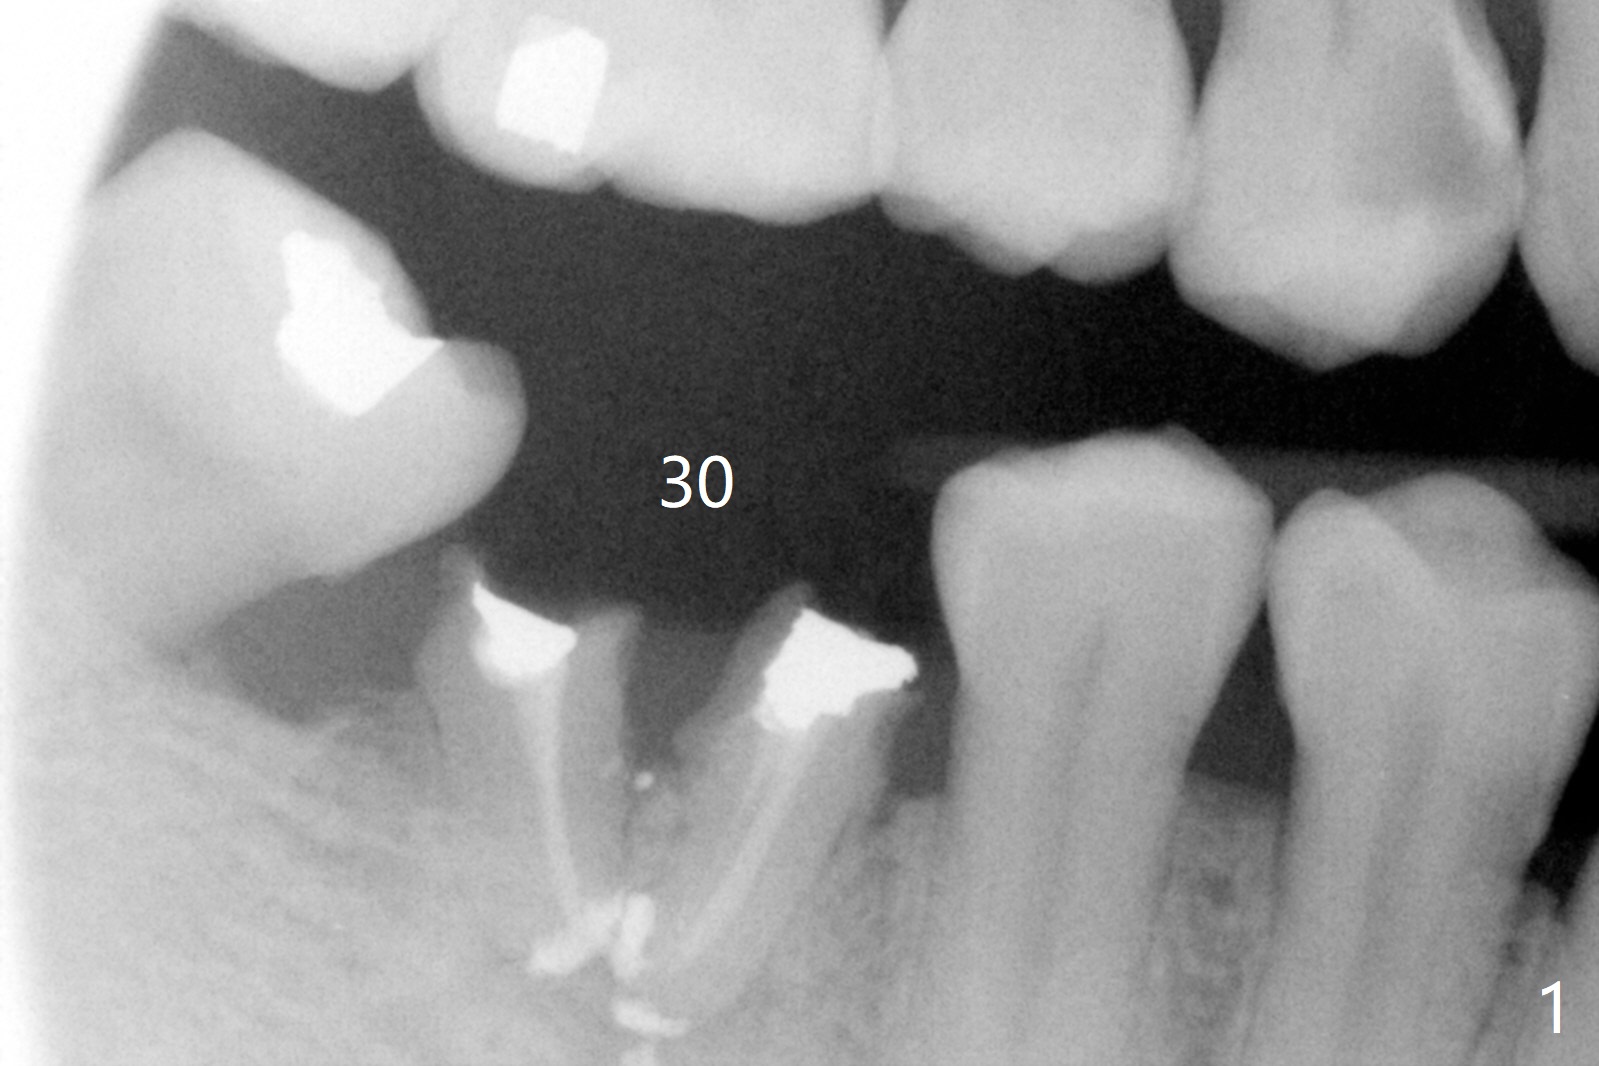

A 50-year-old man has poor dentition, including residual roots at #30 (Fig.1). In 9 years, the residual roots have migrated coronally (Fig.2 arrow). It appears that the bone height increases. Insert periodontal dressing into the mesial undercut of the tooth #31 (post scaling) and around an abutment for retention. Try IS implants if they arrive.